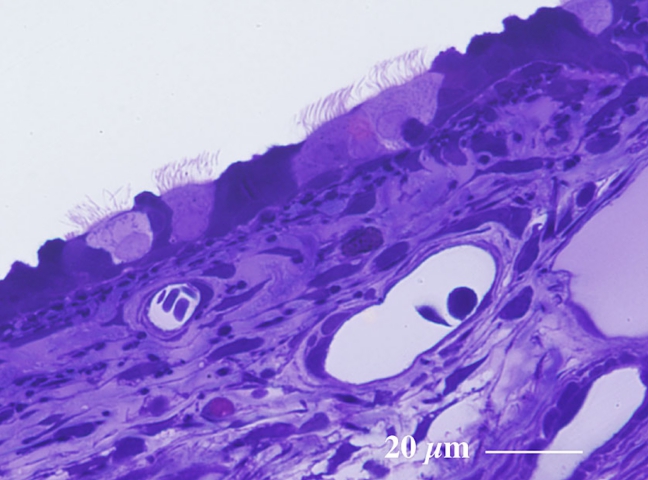

厚さ1 µm エポン樹脂準超薄切片のトルイジンブルー染色光学顕微鏡画像

Light microscopic image of 1 µm-semithin epoxy resin section with toluidin-blue staining

気管には粒子状物質の排除に関与する線毛細胞 ciliated cell が観察されます。

線毛細胞の拡大像